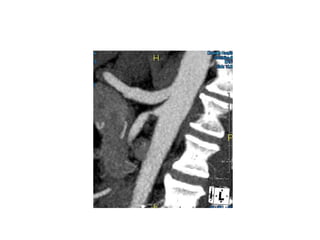

Median arcuate ligament syndrome

 Celiac Artery

Compression Syndrome

 Etiology - Compression

of CA by the median

arcuate ligament.

 Female 20-40 years old

 Symptom - post-

prandial epigastric

abdominal pain

 Treatment - release the

median arcuate

ligament

Angio/CTA